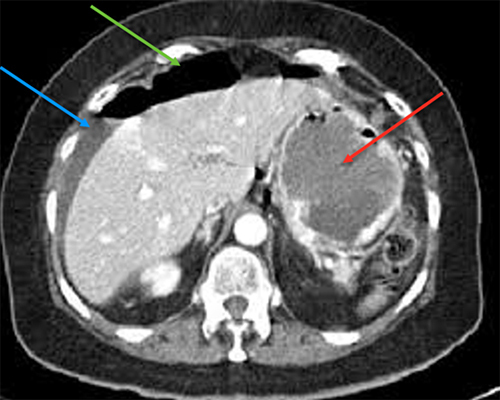

Monsieur A., 53 ans, est adressé aux urgences par son médecin traitant pour des douleurs abdominales fébriles. Celles-ci sont localisées en fosse iliaque gauche et hypogastre. Elles évoluent depuis quelques jours mais sont devenues plus intenses depuis vingt-quatre heures.

Cliniquement, il a une température à 38,2 °C, l’abdomen n’est pas distendu mais la palpation retrouve une franche douleur en fosse iliaque gauche et en hypogastre sans défense. Il n’y a pas de signe fonctionnel urinaire.

Le diagnostic est tout à fait possible, à évoquer ici en première intention devant l’âge (> 40 ans) et la symptomatologie (douleurs fébriles en fosse iliaque gauche et hypogastre).

– de la localisation de la douleur en fosse iliaque gauche ;

– du syndrome inflammatoire : fièvre à 38,5 °C avec hyperleucocytose à la biologie ;

– de l’argument de fréquence de cette pathologie à cet âge (la prévalence des diverticules sigmoïdiens est de plus en plus importante avec l’âge, après 40 ans).